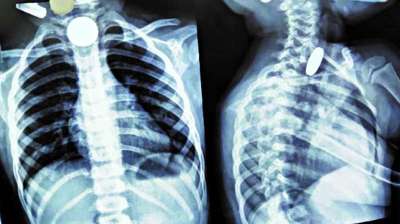

खिलौना नहीं सिक्का था! बच्चे ने निगले 5-10 रुपये के सिक्के, डॉक्टरों ने ऑपरेशन कर निकाले

24 Jul, 2025 04:09 PM IST | CHAMBALCHETNA.COM

दिल्ली : दिल्ली के एक सरकारी अस्पताल के डॉक्टरों ने 12 वर्षीय बच्चे की जान बचाई है। बच्चे ने पांच और दस रुपये के तीन सिक्के निगल लिए थे। सिक्के...